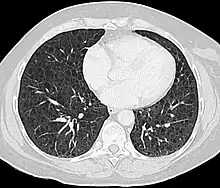

Computed tomography

The high-resolution computed tomography (HRCT) chest scan is better than the chest radiograph to detect cystic parenchymal disease and is almost always abnormal at the time of diagnosis, even when the chest radiograph and pulmonary function assessments are normal.[3][5][6][87] The typical CT shows diffuse round, bilateral, thin-walled cysts of varying sizes ranging from 1 to 45 mm in diameter.[5][6] The numbers of cysts varies in LAM from a few to almost complete replacement of normal lung tissue. The profusion of cysts tends to be milder in patients with TSC-LAM than S-LAM, perhaps explained in part because TSC-LAM patients typically receive earlier screening.[11] Pleural effusions are seen on CT in 12% of patients with S-LAM and 6% of patients with TSC-LAM. Other CT features include linear densities (29%), hilar or mediastinal lymphadenopathy (9%), pneumothorax, lymphangiomyoma, and thoracic duct dilation.[5][6] Ground-glass opacities (12%) suggest the presence of interstitial edema due to lymphatic congestion. In patients with TSC, nodular densities on HRCT may represent multifocal micronodular pneumocyte hyperplasia (MMPH) made up of clusters of hyperplastic type II pneumocytes.[79][88][89] MMPH may be present in males or females with TSC in the presence or absence of LAM, but not in patients with S-LAM.[90] MMPH is not typically associated with physiologic or prognostic consequences, but one case of respiratory failure due to MMPH has been reported.[91][92][93]